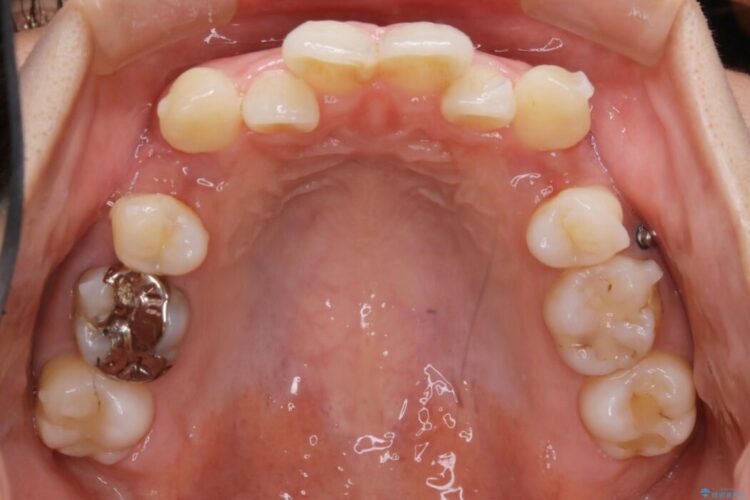

まず噛み合わせに問題が少ない奥歯の位置を極力変えないように上下左右4番目の歯を抜歯することで歯列矯正のためのスペースを確保し、空いた隙間で前歯の凹凸をきれいに並べていくこととしました。

また、ご要望がありマイクロインプラント治療もしています。

笑った時に見えるガタついていた見栄えが改善されて歯列弓もきれいな形に整い、患者様にはご満足いただけました。